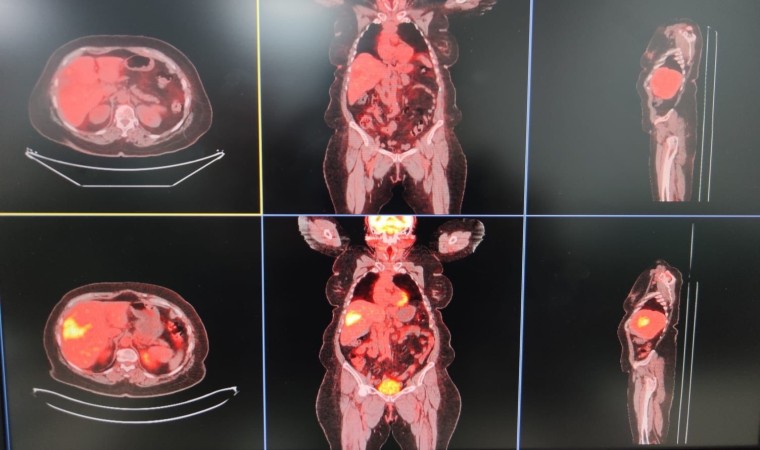

Diyarbakır Gazi Yaşargil Eğitim ve Araştırma Hastanesinde Radyoloji Uzmanı Ayhan Şenol, birimlerinde girişimsel radyoloji olarak hastalıkların tanısı, tedavisi ve takiplerini yaptıklarını söyledi. Hastaların biyopsi, sonografik ve tomografik yöntemlerle tanılarını koyduklarını dile getiren Şenol, “Genel olarak hastalığın bulunması için tüm işlemler yapılabilmekte. Hastalıkların biyopsi veya sonografik-tomografik yöntemlerle hastalıkların tanısını koyuyoruz. Bir kısmının da tedavisini yapıyoruz. TARE işlemi; belli organlardaki tümör hücrelerine hedef kitleyi besleyen damarın içine girip buna lokal olarak radyoembolizan dediğimiz maddenin enjekte edilmesiyle gerçekleşen bir işlemdir. Bu işleme yaygın olarak karaciğerin kendi tümörleri ile başka organlardaki tümörün yayılımlarını tedavi ediyoruz” dedi.

Nükleer tıp birimi ile işbirliği içerisinde hastalara tedavi uyguladıklarını ifade eden Şenol, “Bu servisimizde diğer birimlerle işbirliği yaparak çalışıyoruz. Nükleer tıp en fazla işbirliği yaptığımız birimdir. Hastaların çoğu buraya gelmeden nükleer tıp birimine görünüp öyle bize gelir. Hastanın uygunluğu araştırıldıktan sonra öncesinde burada tedavinin bir provası yapılır. Kitlenin besleyici damarı bulunup buraya bir prova olarak asıl vereceğimiz ilaca benzer bir ilaçla enjeksiyon yapılıyor. Daha sora nükleer tıp biriminde ilacın o kitleyi ne kadar tuttuğu hesaplanıp uygun dozlarda asıl ilaç dozu hesaplanır. Bir sonraki seansta aynı şekilde daha önce belirlediğimiz damarın içine girip radyoembolizan dediğimiz küçük parçacıklara radyoaktif maddeler yüklüyoruz. Biz bu parçacıkları küçük küçük doku içerisine gönderip hem belli bir süre tıkama hem de lokal olarak vücudun diğer taraflarına etki etmeden sadece kitleye etki edip onu öldürme yöntemini kullanarak tümörü tedavi ediyoruz” diye konuştu.